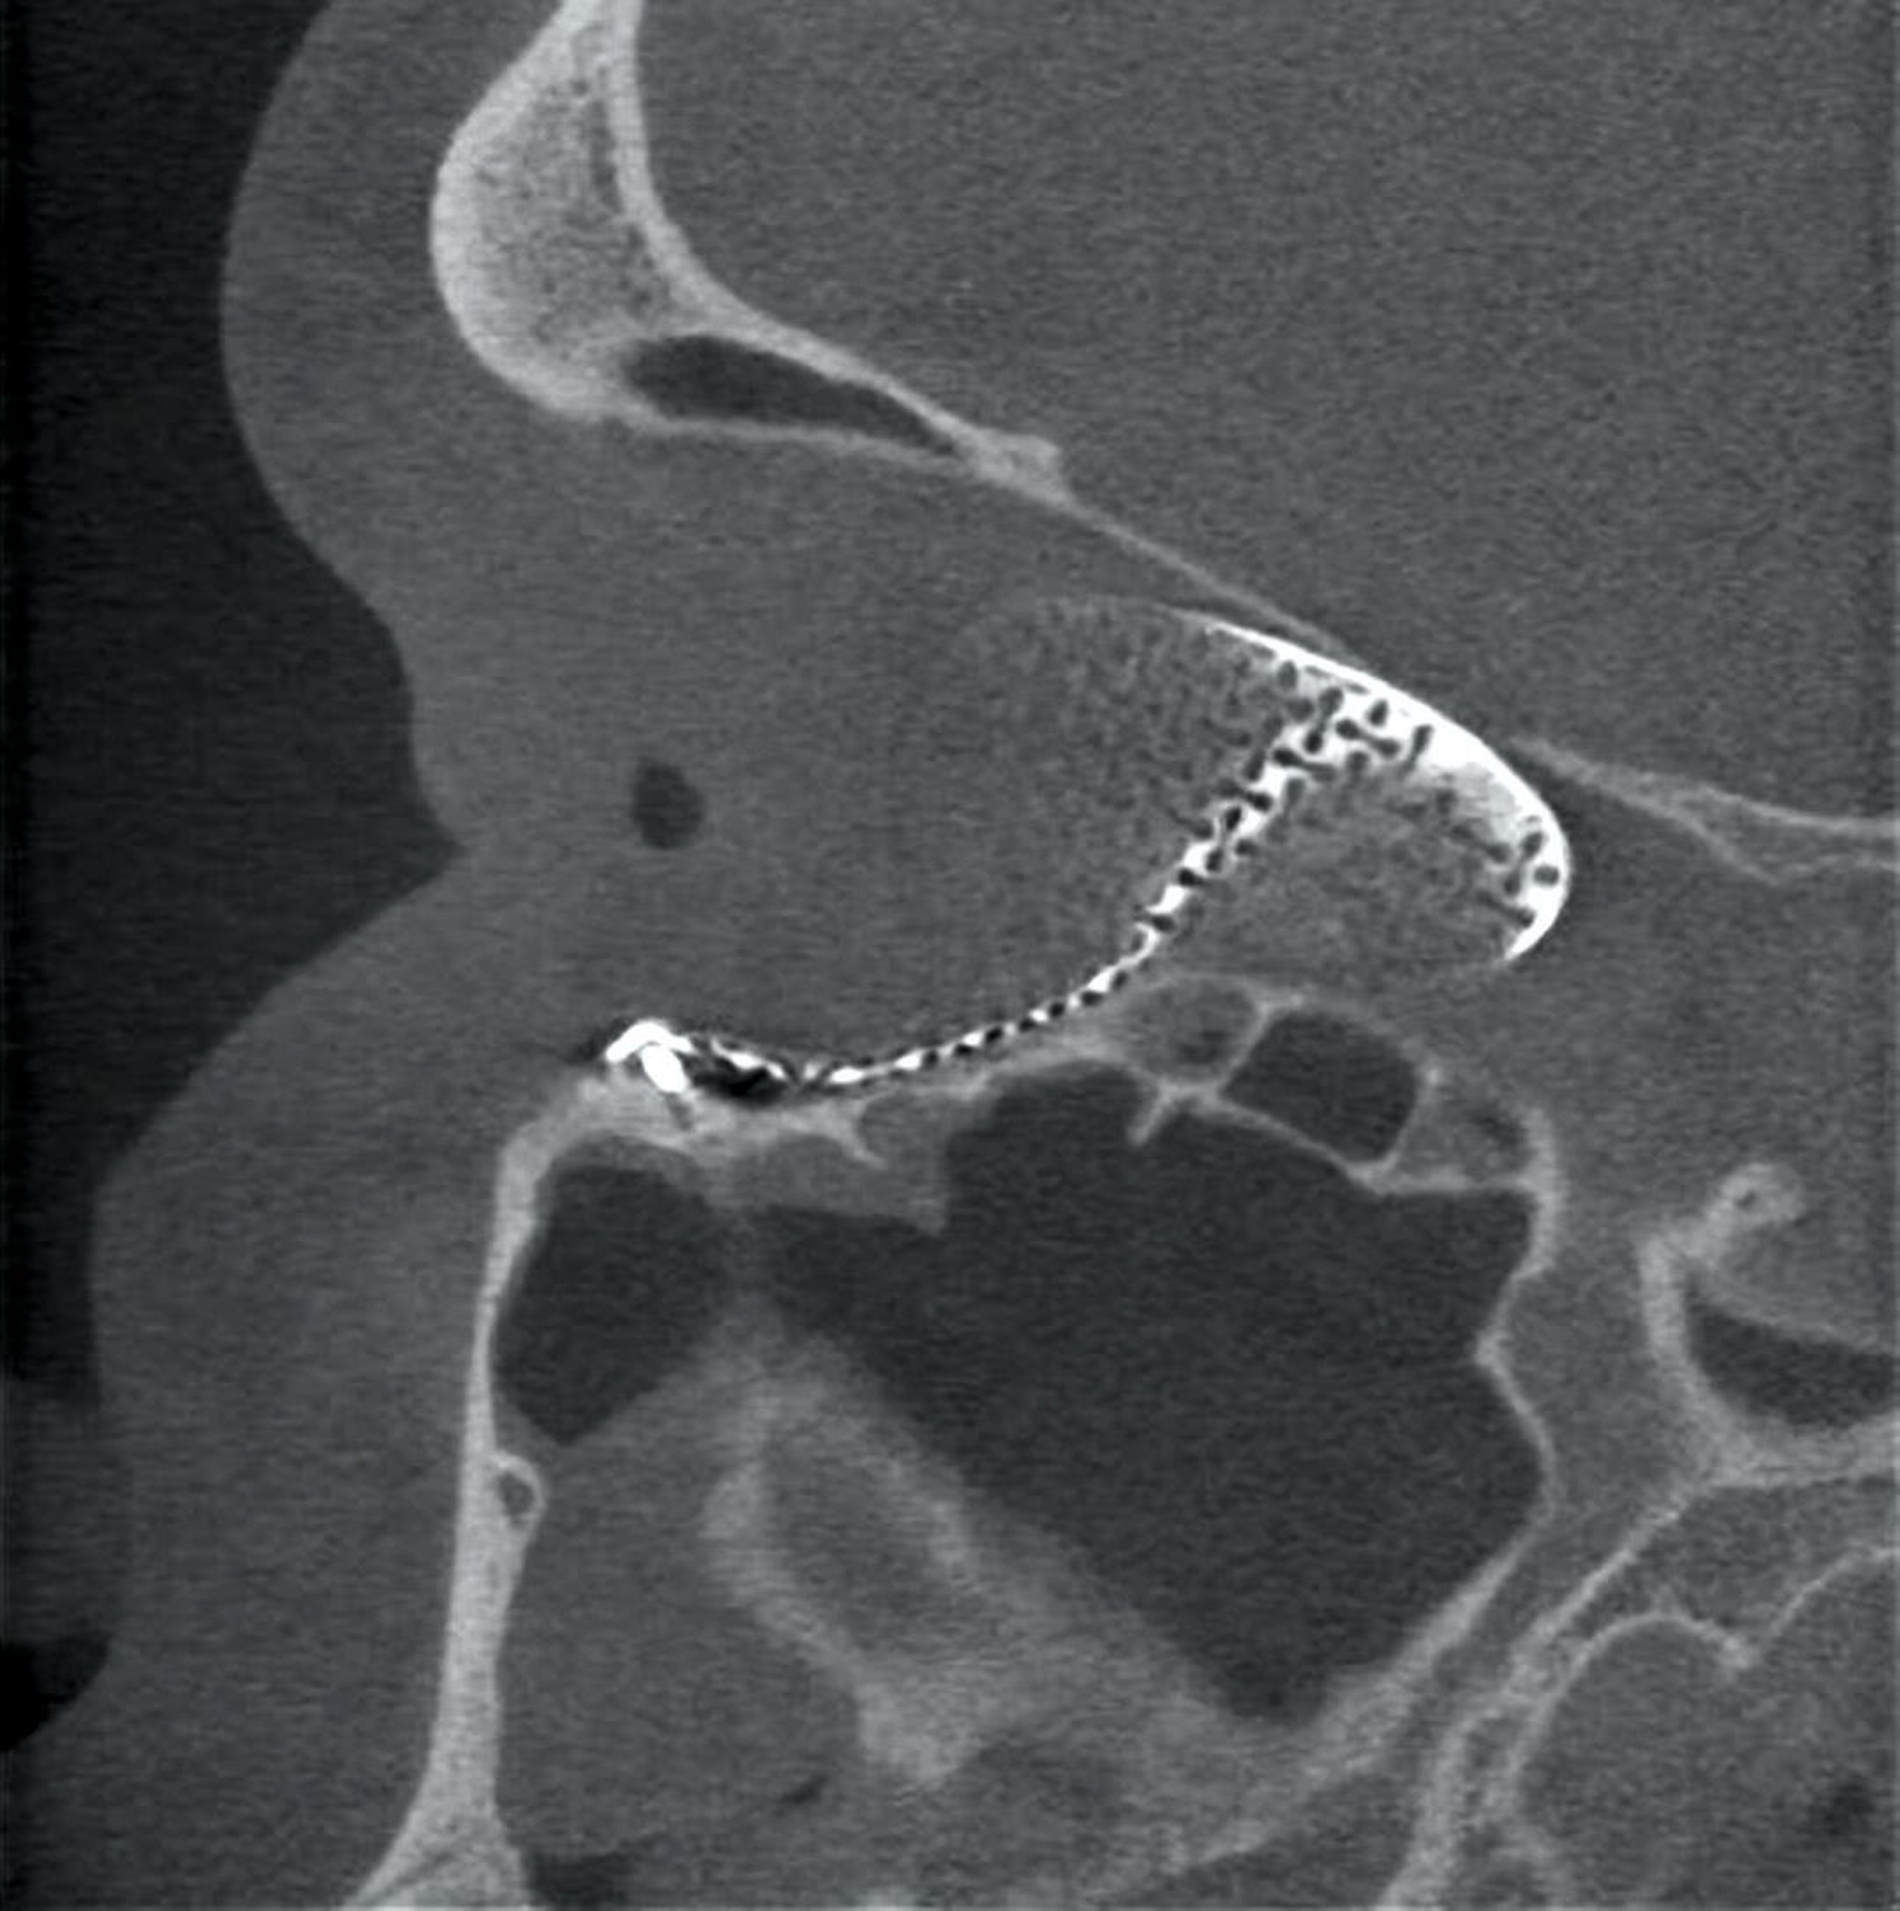

Danach wurde das angefertigte Orbitamesh in Intubationsnarkose über einen transkonjunktivalen-transkarunkulären Zugang zur Rekonstruktion der medialen Orbitawand nach Reposition des in den Defekt dislozierten Weichgewebes eingesetzt (Abbildung 3) und am Infraorbitalrand mit drei Osteosyntheseschrauben fixiert. Die postoperative Bildgebung mittels DVT zur Lagekontrolle zeigte eine korrekte Position des Implantats – entsprechend der präoperativen Planung (Abbildung 4).